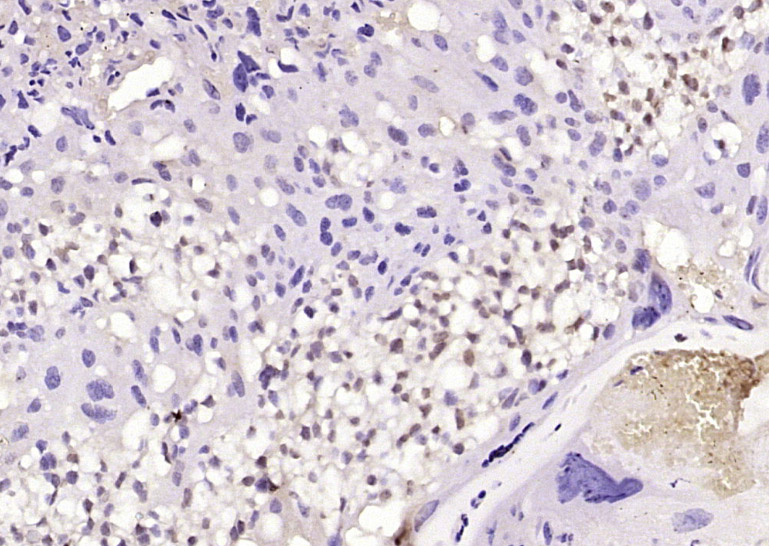

Paraformaldehyde-fixed, paraffin embedded (mouse placenta tissue); Antigen retrieval by boiling in sodium citrate buffer (pH6.0) for 15min; Block endogenous peroxidase by 3% hydrogen peroxide for 20 minutes; Blocking buffer (normal goat serum) at 37°C for 30min; Antibody incubation with (PHD3) Polyclonal Antibody, Unconjugated (bs-0532R) at 1:400 overnight at 4°C, followed by operating according to SP Kit(Rabbit) (sp-0023) instructionsand DAB staining.